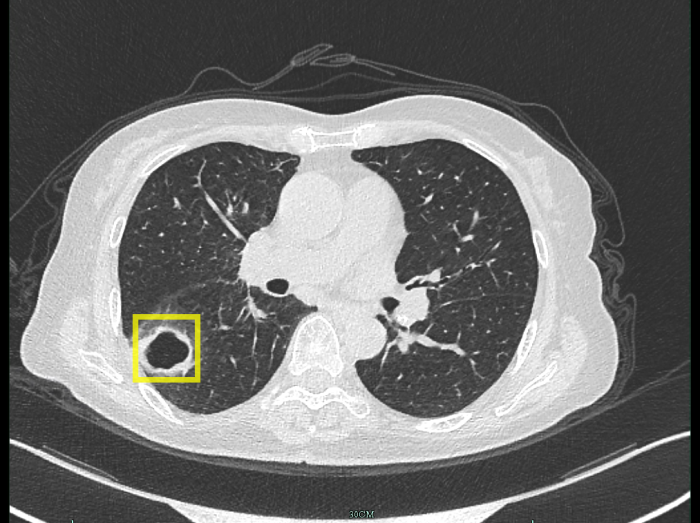

柴阿姨最開(kāi)始以為只是普通感冒,自行吃藥后并沒(méi)有好轉(zhuǎn)。感到焦慮的柴阿姨便到當(dāng)?shù)蒯t(yī)院就診,經(jīng)肺部CT檢查發(fā)現(xiàn),肺部出現(xiàn)空洞病灶。

空洞病灶

迷團(tuán)終于解開(kāi),原來(lái)引起柴阿姨肺部空洞的“罪魁禍?zhǔn)住辈皇欠谓Y(jié)核,而是真菌感染。